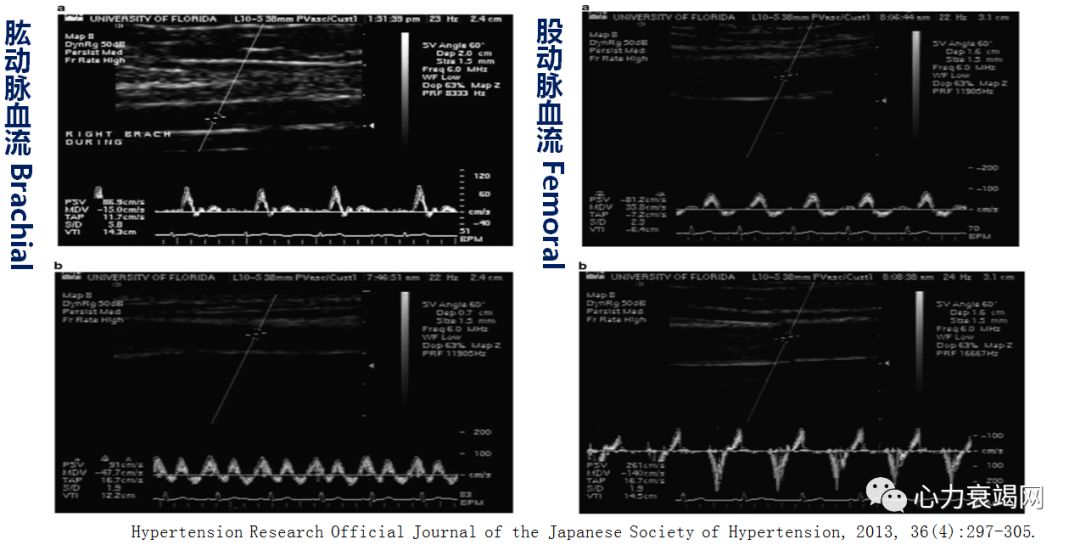

体外反搏的即时血流动力学效应

Acute Hemodynamic Effects of EECP

Increase Coronary Artery Blood Flow

EECP血流动力学效应

——改善外周阻力血管血流